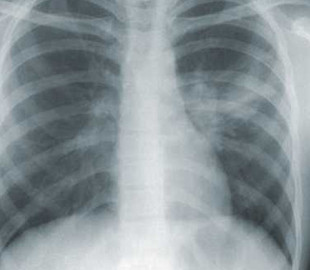

Загадкова пневмонія забрала п'яте життя серед пацієнтів і персоналу клініки на півночі Аргентини. Місцева влада підозрює, що причиною смерті може бути хвороба легіонерів.

Міністерство охорони здоров'я провінції Тукуман оголосило про чотири випадки смерті 3 вересня, всі вони трапилися клініці Сан-Мігель-де-Тукуман. Загалом 11 людей були інфіковані загадковим захворюванням легенів. Симптоми включали блювоту, високу температуру, діарею та болі в тілі.

Захворювання характеризується враженням легенів, протікає, як тяжка пневмонія з високою летальністю (від 5 % до 10 %). Легкі форми (лихоманка Понтіак) схожі на респіраторну вірусну інфекцію з короткочасною гарячкою до 2 – 5 діб, сухістю та болем у горлі.